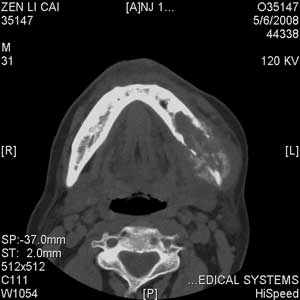

以下是引用jiangjing在2008-5-28 15:56:00的发言:[br]下颌骨左侧部骨质破坏,轻度膨胀,瘤骨形成,软组织肿胀考虑 恶性骨肿瘤-----肉瘤类